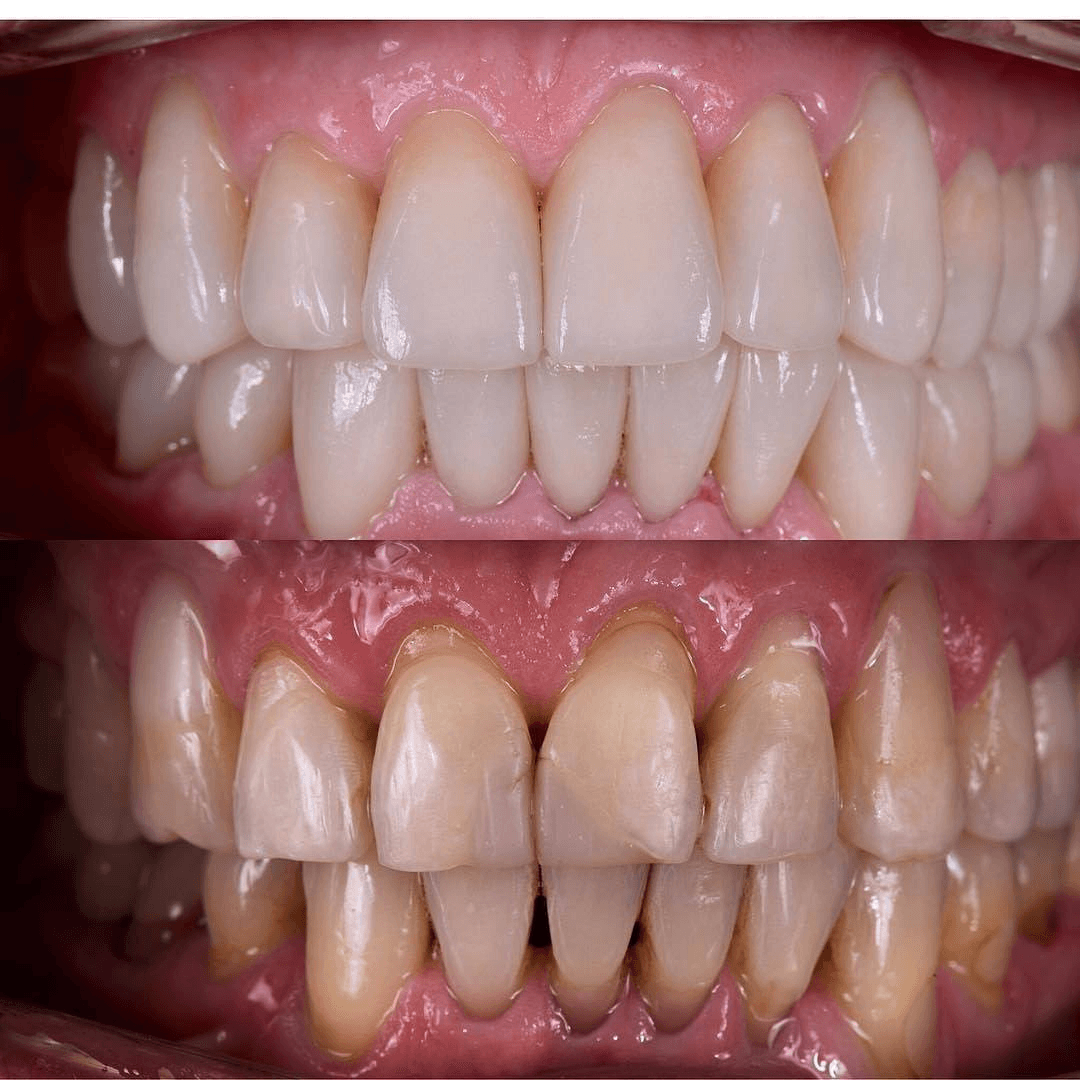

תוצאות - בהסכמה ובטעם טוב

צילומים מהמרפאה - מוצגים בהתאם להסכמות מטופלים ולכללי הפרסום.

חשוב: יש להציג תמונות לפני/אחרי רק בהסכמת מטופלים ובהתאם לכללי הפרסום הרפואי.

צילומים מהמרפאה - מוצגים בהתאם להסכמות מטופלים ולכללי הפרסום.

חשוב: יש להציג תמונות לפני/אחרי רק בהסכמת מטופלים ובהתאם לכללי הפרסום הרפואי.